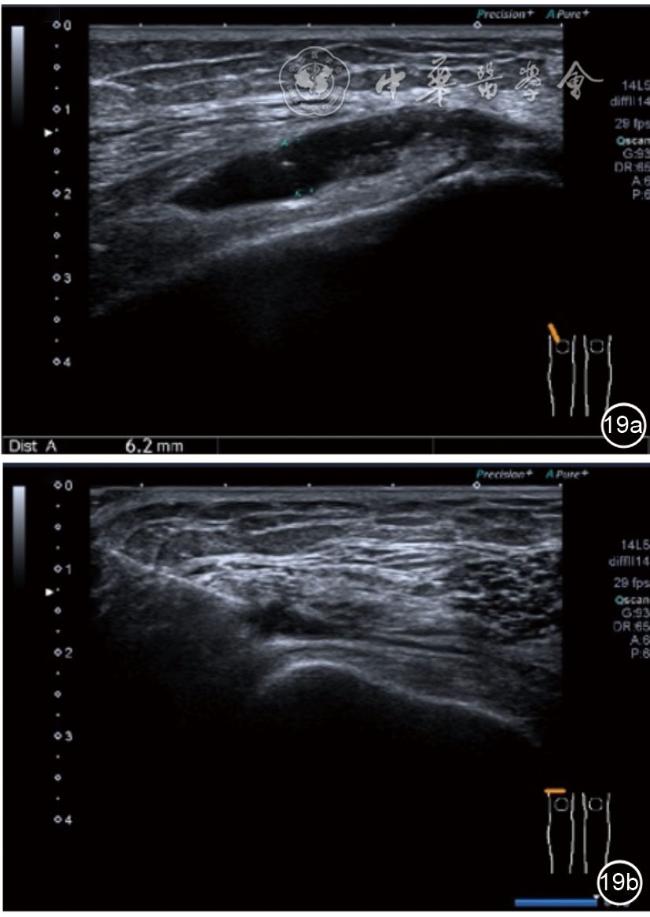

3.膝关节内局部治疗。随着病情发展,静态结构失衡,膝关节内部结构发生变化,会出现软骨损伤、脱落,关节间隙变窄,内外间隙不等,骨赘形成等。膝关节内局部治疗包括关节内症状性骨赘剥离、玻璃酸钠及PRP注射等。(1)膝关节内症状性骨赘针刀剥离松解治疗。由于软骨缺损或者力平衡失调,在关节内脱落软骨区会出现骨赘。部分骨赘引起疼痛,或者与髌骨撞击出现临床症状需要治疗。针刀剥离目的不是去除骨赘,而是剥离松解,缓解或者消除疼痛。以股骨外髁骨赘为例。患者平卧位,膝关节屈曲100°~120°。一般选用10 MHz超声探头,穿刺区域常规消毒,探头涂抹耦合剂后套入无菌手套碘伏消毒或使用无菌耦合剂。将探头置于患者皮肤表面,短轴扫查,显示关节面与骨赘,选用25G注射针,抽吸1%利多卡因3 ml于骨赘周围进行分层麻醉。选用直径1 mm的Ⅰ型2号针刀,在超声引导下从外侧向内侧到达骨赘,反复剥离,一般5~8刀后拔出针刀结束治疗(图18),局部压迫5分钟,无菌敷料覆盖。(2)膝关节髌上囊积液治疗。髌上囊积液在膝关节骨关节炎比较常见,尽管积液量可能很大,但通过软组织松解治疗后,大部分患者积液会减少或者消失。所以积液的治疗可以放在后面处理。超声引导下抽出积液,药物注射是常用的治疗方法。膝关节炎积液的治疗通常包括关节内皮质类固醇激素或者臭氧注射。如果慢性以滑膜丛型增生为主,针刀有限切割增生滑膜加药物注射可提高疗效。①髌上囊积液抽吸加臭氧注射治疗。患者平卧位,膝关节屈曲30°~60°,膝下垫一软枕。选用10 MHz超声探头,治疗前消毒准备同骨赘针刀剥离松解治疗。将探头置于患者皮肤表面,短轴扫查,找到积液最多处,应用22G针头,直接穿刺进入髌上囊抽出液体,然后根据髌上囊大小制备35 μg/L的15~20 ml臭氧注入髌上囊内拔出针头(图19),局部压迫2分钟,无菌敷料覆盖。②髌上囊慢性滑膜炎针刀切割松解治疗。患者平卧位,膝关节屈曲30°~60°,膝下垫一软枕。选用10 MHz超声探头,治疗前消毒准备同骨赘针刀剥离松解治疗。将探头置于患者皮肤表面,长轴或短轴扫查,找到积液最多处,用一次性5 ml注射器抽吸1%利多卡因3 ml于髌上囊进行分层注射麻醉,囊内也要注射适量麻药,尽量抽出积液。选用直径1 mm的Ⅰ型2号针刀,长轴扫查从近端向远端,短轴扫查从外侧向内侧,在超声引导下进入囊肿内对内壁及增生滑膜的不同方向、角度进行反复切割(图20),一般2~3分钟拔出针刀,然后囊内注射1%利多卡因3 ml+曲安奈德15 mg,结束治疗,局部压迫5分钟,无菌敷料覆盖。(3)膝关节腔PRP注射治疗。关节腔注射主要是为了修复软骨,如果不是为了治疗积液,不主张应用激素类药物。目前主要的注射药物为玻璃酸钠、PRP。按照传统的注射部位,多为髌上内、外或者髌下内、外注射点,但是超声不能观察到注射针的位置,药物也不能很好到达软骨损伤的部位,效果受到影响(图21)。膝关节软骨损伤的主要部位在髌股关节的股骨髁,超声可以很好地显示这一部位,并能显示软骨变薄。因此,由这个路径平面内进针注射,可以很好显示穿刺针的路径与位置。以注射PRP为例。患者平卧位,膝关节屈曲100°~120°,选用10 MHz超声探头,治疗前消毒准备同骨赘针刀剥离松解治疗。将探头置于患者皮肤表面,短轴扫查显示关节面,应用25G注射针头,抽吸1%利多卡因2 ml由内侧进针进行分层麻醉直达关节软骨面。制备4.5 ml PRP,直接注射到关节面,液体顺关节面分布,注射完毕拔出针头(图22)。局部压迫2分钟,无菌敷料覆盖。(4)髌骨软化超声影像融合技术下PRP注射治疗。髌骨软化是指髌骨关节面的软骨损伤,软骨下骨囊变,MRI能够明确诊断,但是超声不能显示。应用超声与MRI的影像融合技术,依据MRI明确注射部位,在超声引导下可将药物精准注射到软骨损伤的部位。患者平卧位,膝关节屈曲30°,下面垫一软枕。一般选用10 MHz超声探头,治疗前消毒准备同骨赘针刀剥离松解治疗。将MRI的原始图像数据导入超声设备中,进行手动影像融合,完全融合后,确定穿刺靶点,以MRI图像为目标,以超声图像为实时引导进行穿刺,到达目标后,注射提前制取的PRP 3 ml(图23),注射完毕拔出针头,局部压迫3分钟,创可贴覆盖。

图19 超声引导下髌上囊积液抽吸加臭氧注射治疗